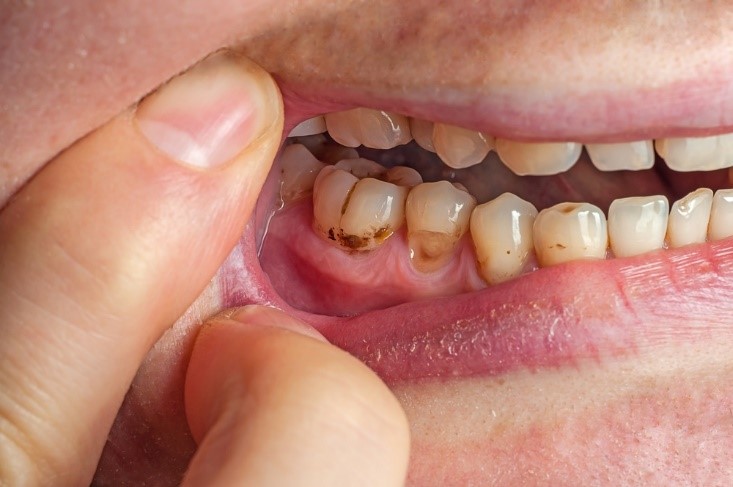

Sâu chân răng là tình trạng sâu răng xảy ra ở vùng chân răng nơi tiếp giáp giữa răng và nướu. Sâu chân răng thường gặp phổ biến ở người trung niên. Bệnh lý này gây ra những cơn đau nhức, khó chịu và dẫn đến nhiều tác hại nguy hiểm nếu không được phát hiện và điều trị kịp thời.

Do vị trí của chân răng là nằm dưới đường viền nướu nên rất khó quan sát. Mặt khác, khi ở giai đoạn khởi phát triệu chứng của chúng thường không rõ ràng nên rất khó phát hiện và chữa trị kịp thời.

(Sâu chân răng diễn biến âm thầm nhưng gây ra nhiều biến chứng rất nghiêm trọng)(**)